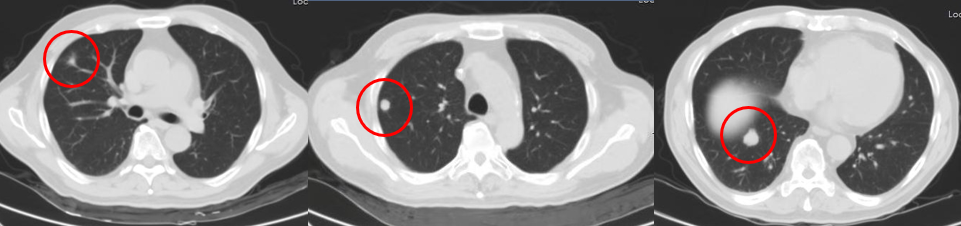

影像评估(PD)

2017.10.25

2018.1.22